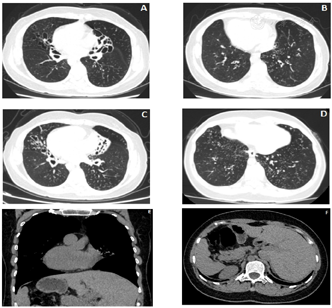

(2)胸部CT检查:双肺支气管管壁增厚,管腔呈囊状或柱状扩张,沿支气管束周围可见多发小斑片及小结节影,局部呈"树芽征"改变。心脏各房室及大血管位置完全反转,所扫范围内上腹部内脏反位(图2)。

影像检查是Kartagener综合征重要的检查手段。胸部CT可明确表现支气管扩张及内脏反位。肺部CT征象通常表现为支气管壁增厚、扩张,管腔内可见粘液栓或痰栓形成,以柱状或囊柱状多见,可见"印戒征""轨道征""蜂窝征""棒状""水滴"等各种征象,大部分分布于双下肺,支气管扩张程度通常与肺功能、年龄有关[14],陈小琴[15]等研究表明发病年龄越早,病史越长的患者的肺部CT表现的慢性支气管扩张导致的肺组织损伤越严重,甚至导致肺间质纤维化,临床症状也越典型。近年来有多项研究指出,弥漫性泛细支气管炎(Diffuse panbronchiolits, DPB)可能是Kartagener综合征的特征表现之一,其在影像学上表现为两肺多发小结节、线样影及树芽征。

胸部扫描还可以看到明确存在全内脏反位:主要表现为患者右位心、纵隔内血管转位、腹部脏器肝脾胃镜面转位。鼻窦或头颅CT可以明确诊断副鼻窦炎及了解窦鼻骨质结构。可观察鼻窦黏膜增厚及密度增高影,鼻腔内息肉、鼻窦窦壁骨质增生或邻近骨质变薄等征象。部分患者可看到中耳炎表现。